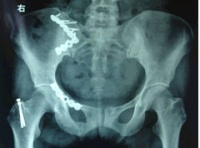

放射学检查[编辑 | 编辑源代码]

(1)骨盆后前位X线片:X线平片检查一般可明确骨折部位骨折类型及其移位情况,亦常能提示可能发生鵻的并发症。全骨盆后前位X线片可显示骨盆全貌对疑有骨盆骨折者应常规拍摄全骨盆后前位X线片以防漏诊对骨盆后前位X线片上显示有骨盆环骨折者,为明确了解骨折移位情况还应再摄骨盆入口位和出口位片。(2)骨盆入口位片:患者仰卧,X射线从颅侧投向尾侧,与片盒成60°倾斜摄片本位片可显示耻骨段骨折移位;骨盆向内、向外旋转和向内移位的程度;骶髂关节向后移位及骶骨骨折是否侵犯椎管;同样可显示坐骨棘撕脱骨折。

(3)骨盆出口位片:X线是从尾侧投向颅侧,与片盒成45°角本片可显示桶柄型损伤与耻骨体骨折,对确定半骨盆有无向上旋转移位是很有用的,在本片上同样可显示骶骨或髂骨骨折移位情况。

CT检查对骨盆骨折虽不属常规但它可在多个平面上清晰显示骶髂关节及其周围骨折或髋臼骨折的移位情况,因此凡涉及后环和髋臼的骨折应行CT检查骨盆三维重建CT或螺旋CT检查更能从整体显示骨盆损伤后的全貌,对指导骨折治疗颇有助益但应铭记对血流动力学鵻不稳定和多发伤患者,后前位全骨盆X线片是最基本和最重要鵻的放射学检查不要在拍摄特殊X线片上花费时间,更为重要的是尽快复苏。